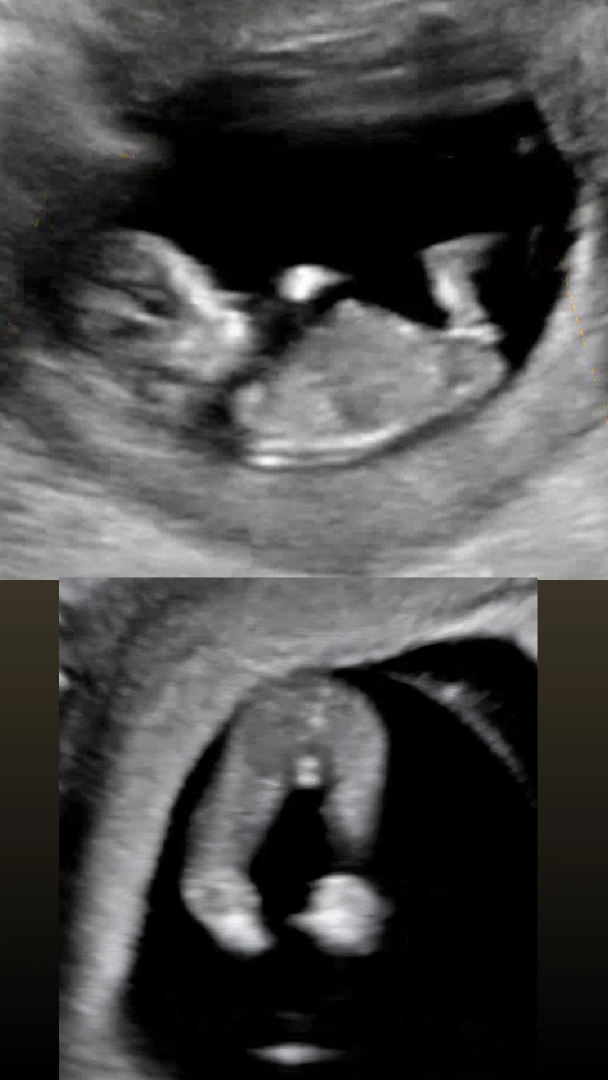

11주 5일차 각도법 고수님들 투표 부탁드립니다

안녕하세요 11주 5일차에 1차 기형아 검사를 받게된 예비맘입니다 장꾸맘에 각도법 문의하고싶었는데 12주 이상부터 가능하다고 해서요 ㅠㅠ 혹시 고수님들 의견 가능할까요 각도법 공부하고 보니 평행해서 딸 같은데 다리사이에 뭐가 있어서 고추인가? 했어요 공부하다보니 아들은 삼각점이 보이고 딸은 죠리퐁이다 라고 하더라고요 정보가 많이 없어서 문의드려요! 저는 아들딸 상관없고 남편이 딸을 원해요ㅠㅠ 2차 기형아검사까지 시간이 너무 안가네용 부탁드립니다! ----------------------------후기 딸입니닷 투표 감사합니다 😍